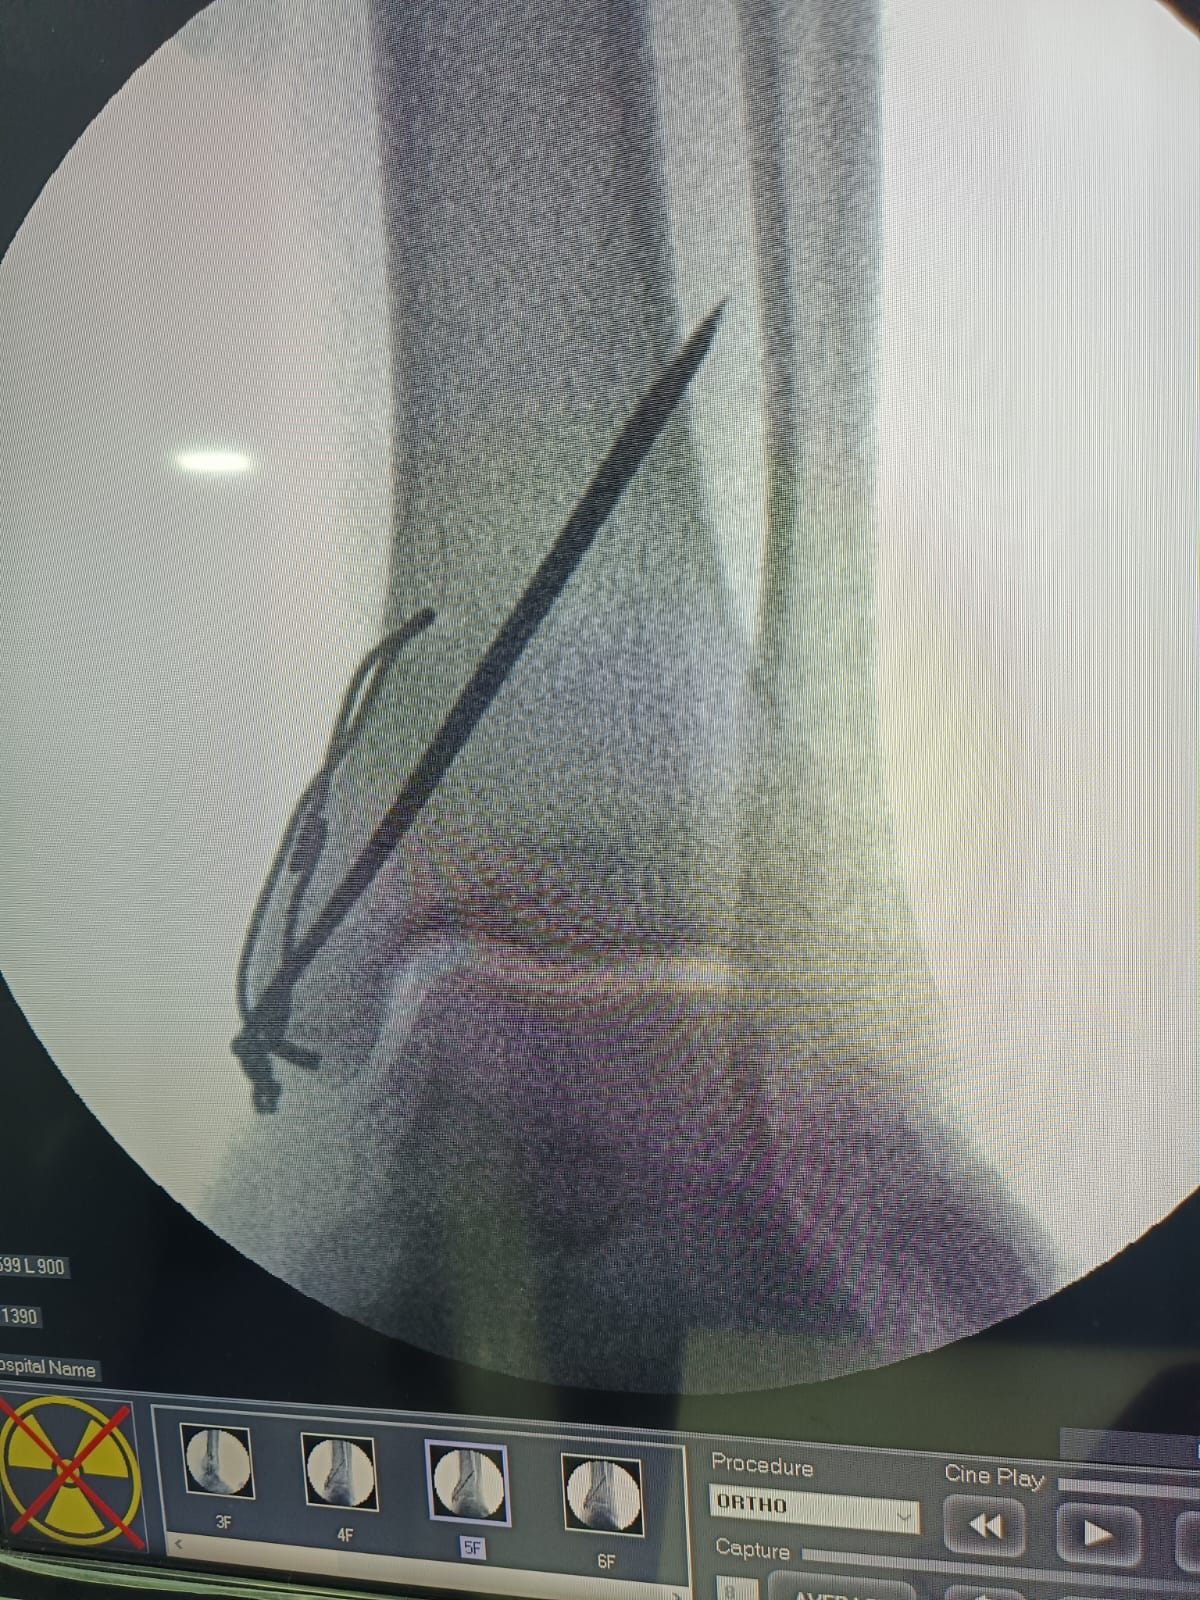

Fracture and Trauma Surgery

- Fellowship in Foot and ankle surgery at Ashoka Medicure hospital Nasik Maharashtra